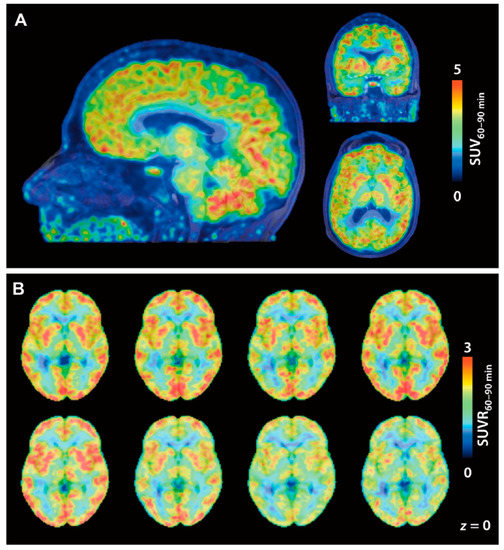

- Wey, H.Y.; Gilbert, T.M.; Zurcher, N.R.; She, A.; Bhanot, A.; Taillon, B.D.; Schroeder, F.A.; Wang, C.; Haggarty, S.J.; Hooker, J.M. Insights into neuroepigenetics through human histone deacetylase PET imaging. Sci. Transl. Med. 2016, 8, 351ra106. [Google Scholar] [CrossRef] [PubMed]

| [18F]12 | HDAC6 | Excellent brain uptake (SUV ≈ 3 around 30 min p.i.) was observed in baboons Nonspecific binding in the brain determined with 1 mg/kg unlabeled 12 was low (<1 SUV) | [80] |